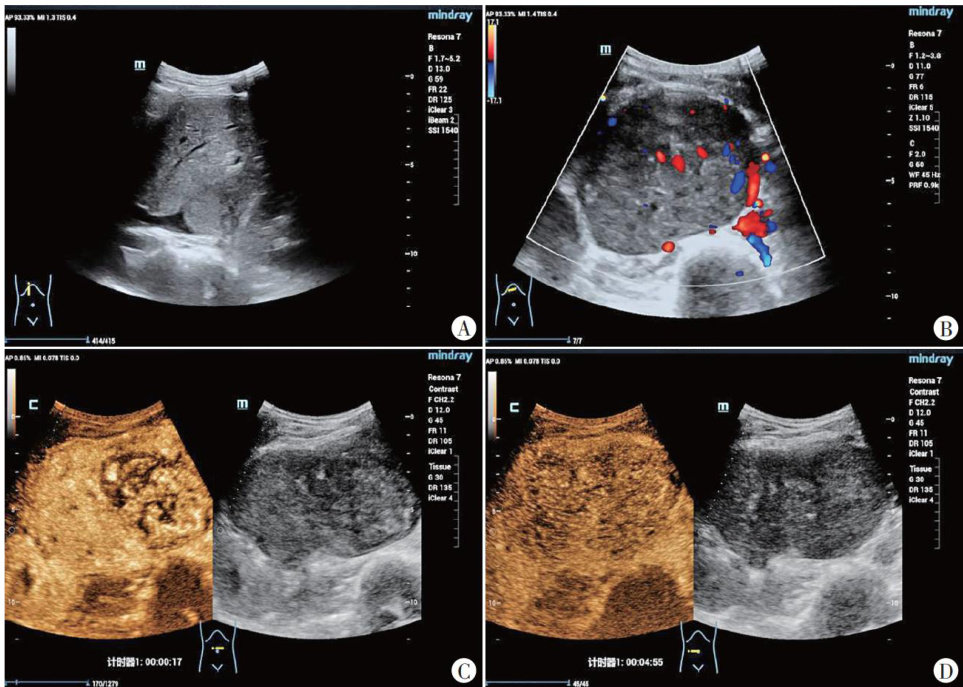

下腔静脉平滑肌肉瘤超声表现1例

患者女,26岁,因“扪及右下腹包块 4+ 个月”入院。体格检查:腹部略膨隆。实验室检查:糖类抗原 19-949.40U/ml ,乙肝表面抗体定量 22.8U/L ,降钙素原 0.319ng/ml ,氧合血红蛋白浓度97.5% ,全血碱剩余 3.2mmol/L ,细胞外液碱剩余 3.7mmol/L ,缓冲碱 49.2mmol/L ,氧分压 122.3mmHg(1mmHg=0.133kPa) ,碳酸氢根 28.1mmol/L ,甲胎蛋白、癌胚抗原、糖类抗原125、热休克蛋白 90α 、血儿茶酚胺及代谢酚均呈阴性。(剩余3447字)